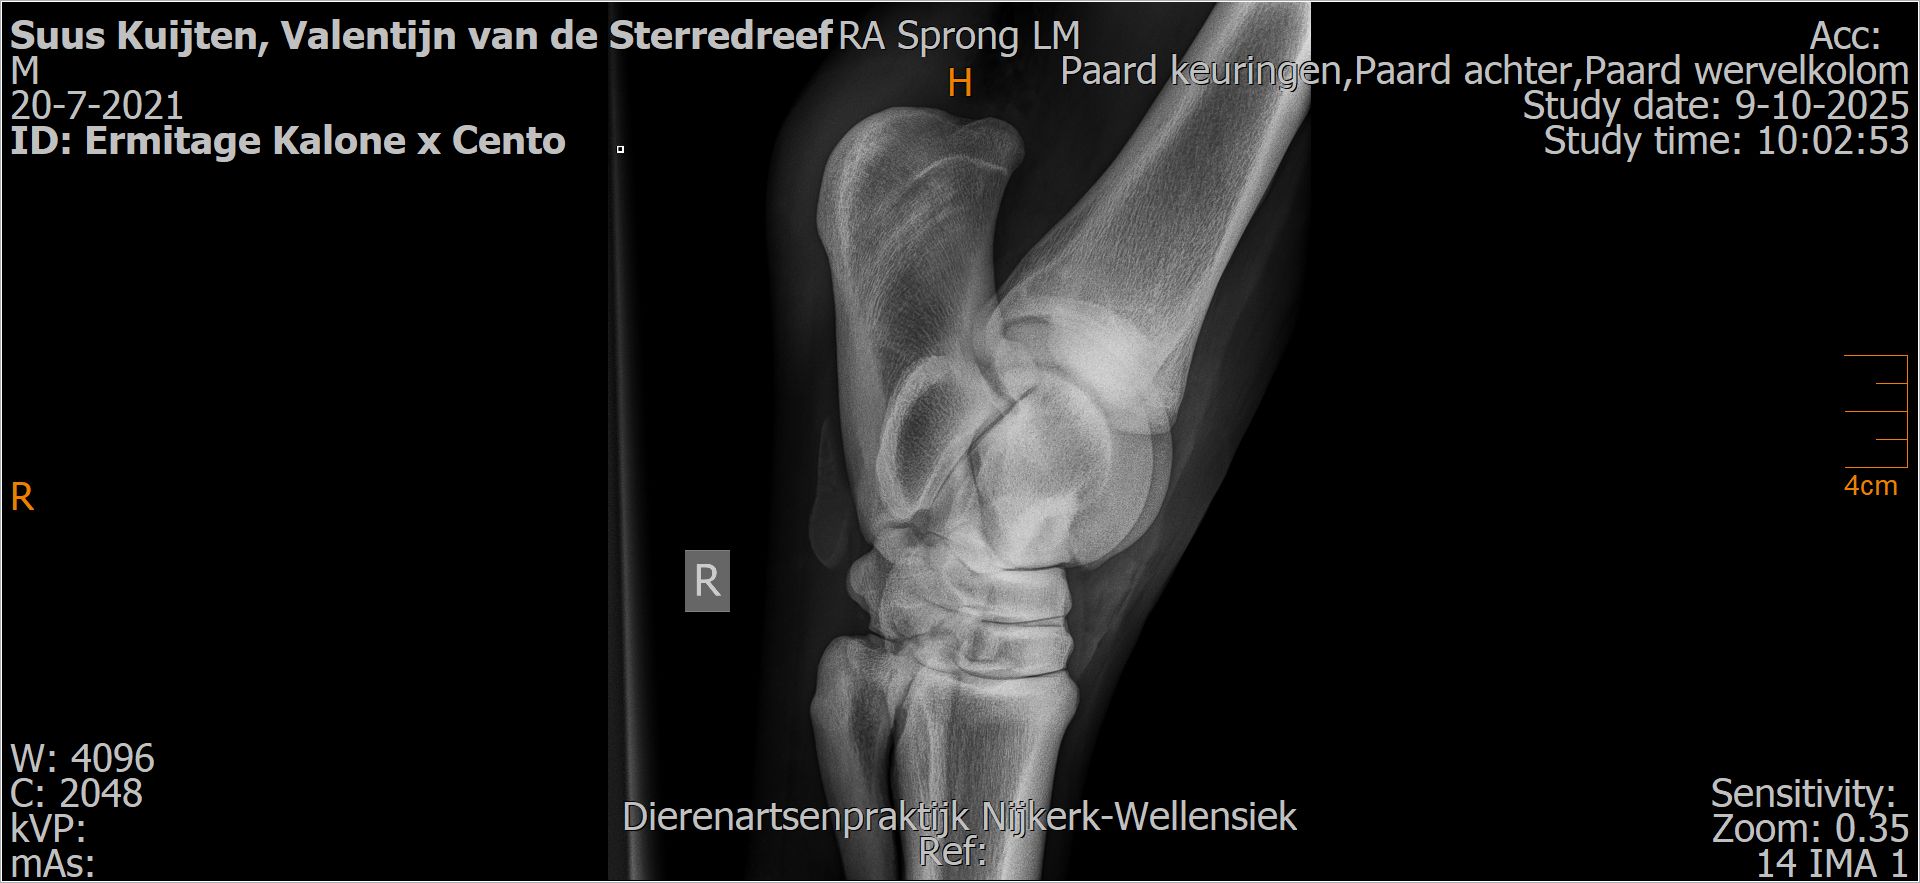

Valentijn van de Sterredreef

Leeftijd:

4

Röntgenfoto’s